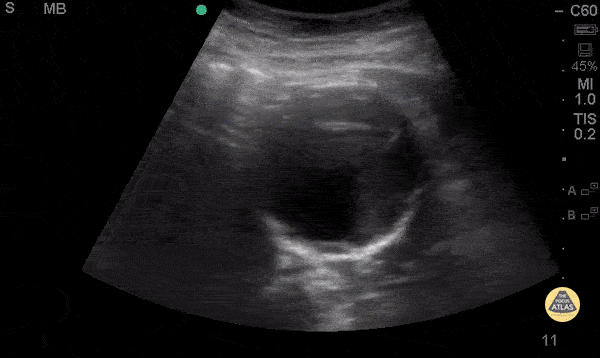

Aorta - Mural Thrombus in AAA

74 y/o F hx stage 4 lung cancer, AAA, presented with chest pain and SOB x 1 day. POCUS shows the aorta is larger than the normal diameter of 3 cm, representing an abdominal aortic aneurysm, and measuring approximately 5.6 cm at its largest point. On cross section you are able to see a large mural thrombus with decreased diameter of blood flow through the center. Juliana Jaramillo MD - Kings County Emergency Medicine